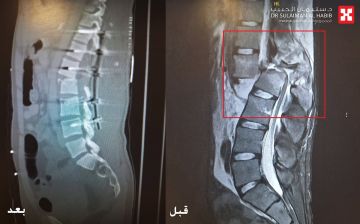

تمكن مستشفى الدكتور سليمان الحبيب بالريان، من إجراء عملية معقدة لإنهاء معاناة مراجع يبلغ من العمر 22 عاماً، أصيب بالشلل التام نتيجة تعرضه لحادث سير مروع سبب له كسر حاد في العمود الفقري والعديد من الإصابات المتفرقة بالجسم. ذكر ذلك الدكتور مارون أبو ناضر استشاري جراحة المخ والأعصاب والعمود الفقري، رئيس الفريق الطبي المعالج الحاصل على شهادة الاختصاص الفرنسية في المناظير الجراحية.

والذي أضاف بأن المراجع وصل قسم الطوارىء بالمستشفى عبر الهلال الأحمر، عقب إصابته بالحادث، يعاني من آلاماً شديدة وإصابات متعددة في الوجه والبطن والأطراف وتورمات في كامل الجسم. على الفور تم تقديم الإسعافات الأولية وإجراء فحوصات بأشعة الرنين المغناطيسي (M.R.I) والأشعة المقطعية (C.T Scan) والأشعة السينية الرقمية (Digital X-rays)، والتي بينت وجود كسر في الفقرة القطنية الأولى وتحطم عظم الفقرة الثانية من الخلف (L1-L2)، وكذلك نزوح الفقرات وإنضغاطها وتغير مكانها نتيجة قوة الحادث، بالإضافة إلى وجود قطع وتهتك في غشاء الأعصاب بالعمود الفقري، الأمر الذي أدى لشلل كامل الأطراف السفلية.

موضحاً أن الفريق الطبي المكون من استشاريي جراحة العمود الفقري والمخ والأعصاب، والطوارىء والعناية المركزة والتخدير، عقب دراستهم للحالة إتخذوا القرار بالتدخل الجراحي العاجل، حيث تم نقل المراجع مباشرة إلى قسم العمليات، مفيداً بأن العملية استغرقت 7 ساعات متواصلة تحت التخدير العام، وتم فيها إعادة فقرات العمود الفقري إلى موضعها الصحيح وإصلاح الفقرة الثانية القطنية، ومعالجة غشاء الأعصاب كلياً، تبع ذلك إعادة الأعصاب المصابة إلى مكانها الطبيعي بصعوبة شديدة، نقل بعدها الى العناية المركزة (I.C.U).

وقال الدكتور مارون أن جهود الفريق الطبي تكللت بالنجاح ولله الحمد، إذ تحسنت المؤشرات الحيوية للمراجع خلال 48 ساعة من العملية، وفي اليوم الرابع خرج لجناح التنويم بعد تمكنه من تحريك أصابع القدمين بشكل تدريجي، وبمرور 4 أسابيع من التأهيل الطبي المكثف والمتابعة الحثيثة، استطاع تحريك الأطراف السفلية وعضلات الحوض، موضحاً أن المرضى اللذين يتعرضون للكسور الحادة في العمود الفقري، عادة ما يستغرقون وقتاً طويلاً لإستعادة كامل الحركة.